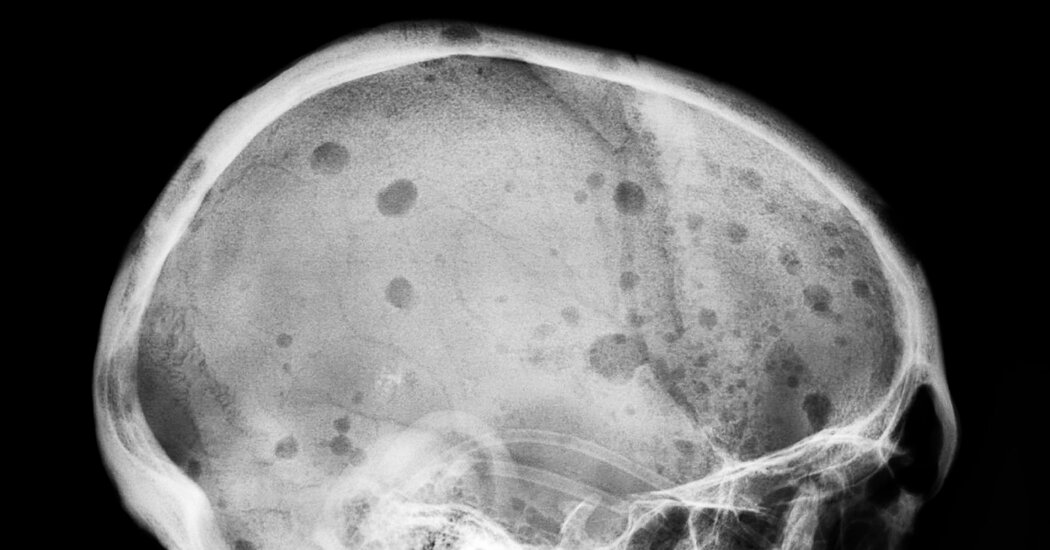

A group of 97 patients had longstanding multiple myeloma, a common blood cancer that doctors consider incurable, and faced a certain, and extremely painful, death within about a year.